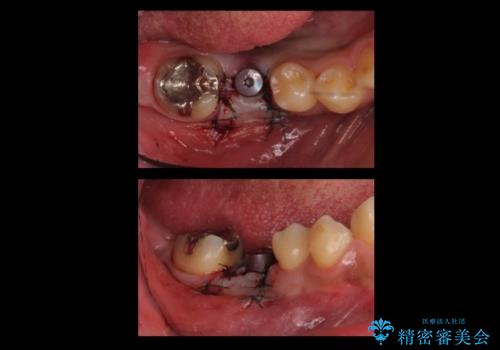

手術が怖いとのことで、外科手術時には静脈麻酔を行い、眠っている間に手術が終わるようにしました。

インプラントの術式は比較的単純で、難しくないですが、予後を見据えて角化歯肉を増やす手間をかけることが大変重要です。

- 52万円 内訳:ストローマンインプラント(1本)42万円(仮歯、ジルコニアクラウン、カスタムアバットメント含む) 静脈麻酔 5万円x2回費用は治療当時の料金となります

インプラント手術時に同時に親知らずの抜歯も行い、腫れや痛みなどを1度で終わらせるようにしました。